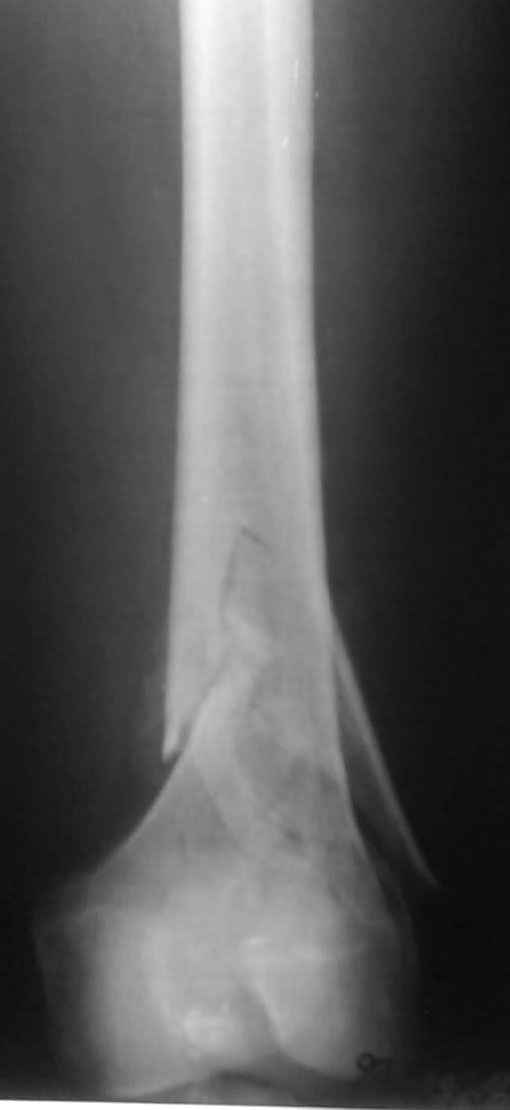

Привет из Нижнего Новгорода! К нам поступил пациент 25 лет с закрытыми переломами обеих бедренных костей, прошел месяц после травмы. Слева - внутрисуставной перелом, поэтому выбор здесь очевиден, открытая репозиция, стабильная фиксация, скорее всего LCP DF, а справа - мнения учёных, как говорится, разошлись. Лично я, как лечащий врач, за закрытый интрамедуллярный остеосинтез DFN. Со мной согласна половина коллектива, другая - за интрамедуллярный остеосинтез (DFN,UFN) но с открытой реопозицией, поскольку при закрытой методике все осколки останутся где-то сбоку, получится дефект и вдруг не срастется!Философский вопрос: что лучше - красивая рентгенограмма или сохранение кровоснабжения? Очень важно мнение коллег! Смирнов Алексей

Уважаемые коллеги! От имени Алексея Смирнова всем спасибо за обсуждение. Больной прооперирован. Снимки в приложении.